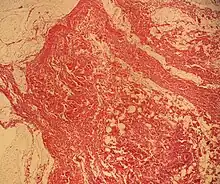

Histopathology of a lipoma: The mass is composed of lobules of mature white adipose tissue divided by fibrous septa containing thin-walled capillary-sized vessels.[23]